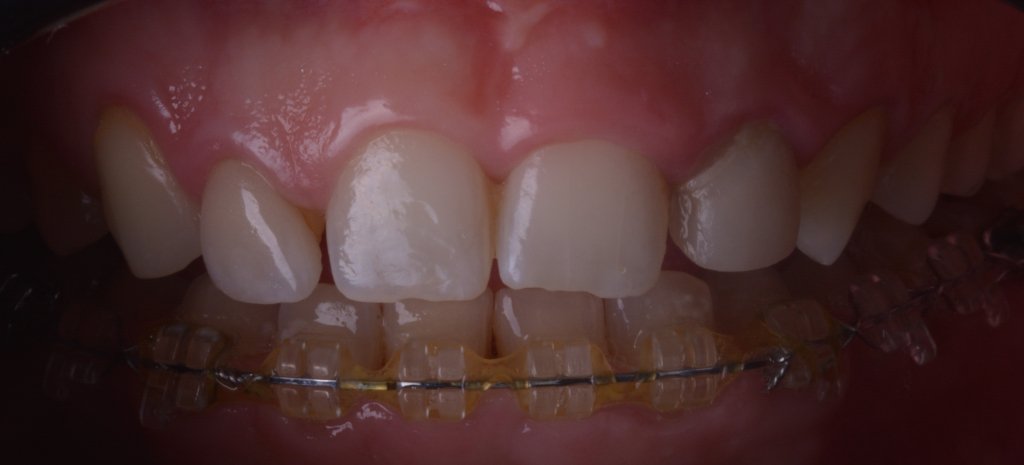

Y vamos de Azul (NIC TONE) sin linea de terminación, sufrimos el doble..no tenemos donde agarrar el Clamp y sobre todo donde realmente termina la carilla…

Voy siempre de 2 en 2, claramente cemento antes las Coronas, que me ayudaran a «clampar» y luego las carillas. Pero normalmente empiezo con los laterales que están en el medio y suelen robar el espacio a los otros

Tomaros vuestro tiempo para limpiar bien bien, no os vais a arrepentir en la vida..

Keep calm trás la retirada del Dique, esta encía volverá a su sitio (si habéis hecho bien la cirugía por supuesto).